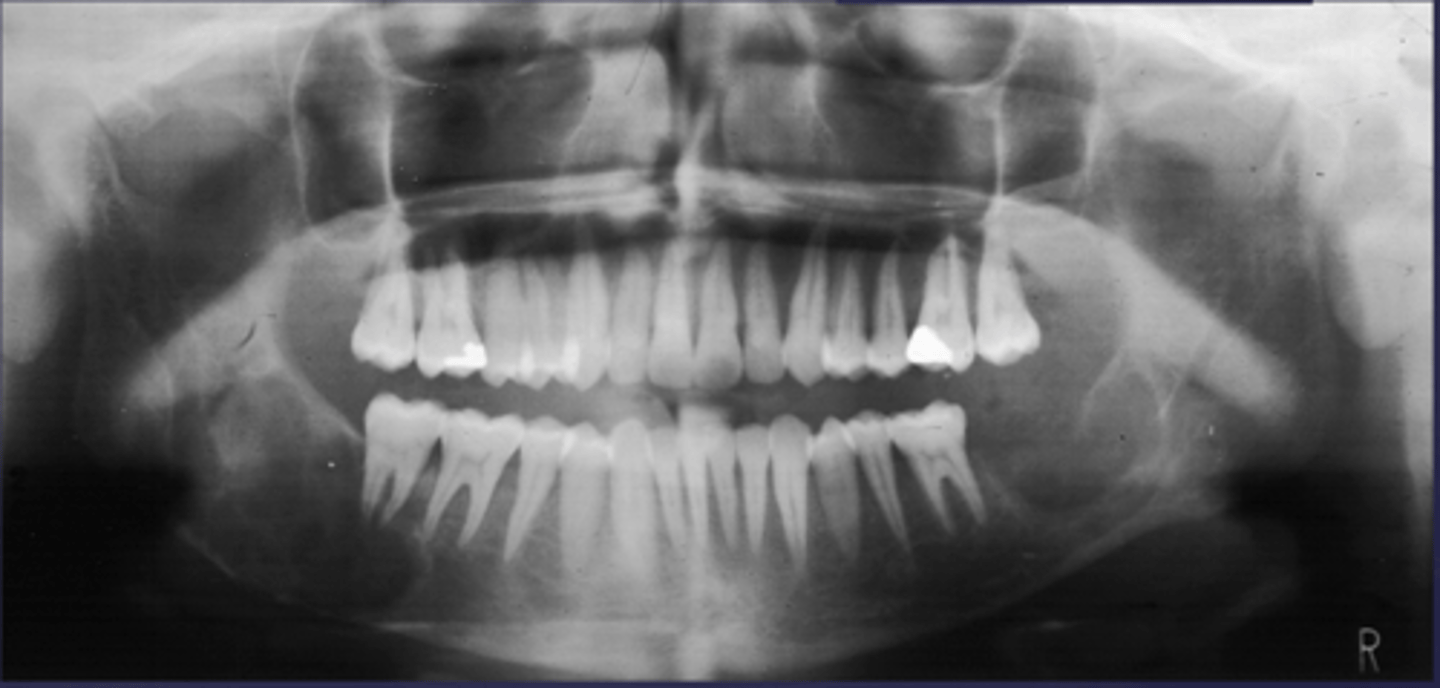

How would you describe the lesion?

Multiple multi-focal coalescing target-like radiopacities in multiple quadrants

What category would this lesion be part of?

Dysplasia

What would be a differential diagnosis for this lesion?

Florid cemento-osseous dysplasia

- Ill defined, moth-eaten trabecular pattern in the entire mandible

- There is chronic periodontal bone loss associated with most mandibular teeth with furcation involvement and apical radiolucencies

- There is thinning of the inferior mandibular cortex.

- Can also be described as ill-defined areas of mixed radiolucent and radiopacities throughout the

mandible

Inflammation/Malignant

Chronic osteomyelitis

(DD: osteomyelitis, multiple myeloma)